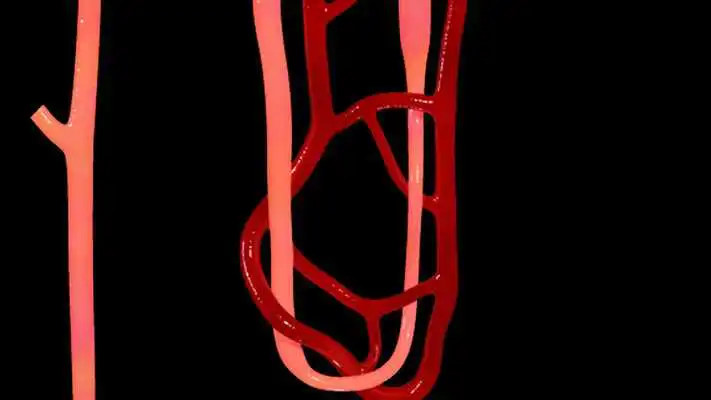

Nephron Blood Vessels 3D

Nephron Blood Vessels 3D

DESCRIPTION

Play this online game named Nephron Blood Vessels 3D.

Nephron Blood Vessels 3D - Key Features :1) You can Zoom and Rotate the 3d model.

2) Take apart to understand the anatomy better.

3) Each layer or object can be made Glassy to see through.

4) Label or Title every object or layer.

5) Analyse feature allows educators for show special focus on a specific part.